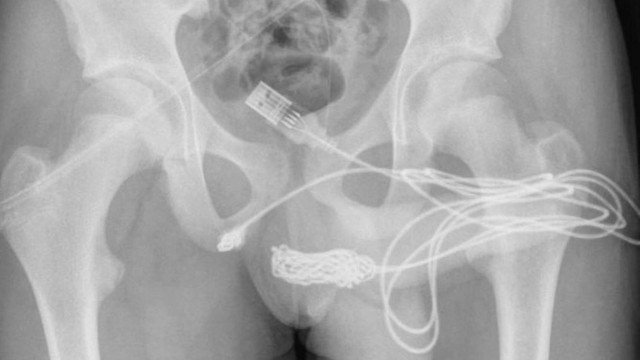

Um caso nada comum foi relatado num estudo publicado no último sábado (11/9) na revista médica Urology Case Reports: um adolescente de 15 anos do Reino Unido teve que passar por uma cirurgia de emergência depois que um cabo USB ficou preso em sua uretra quando tentava medir o tamanho do pênis.

De acordo com o jornal americano New York Post, o incidente supostamente começou depois que um menino de 15 anos, que não teve a identidade revelada, claro, foi levado pela curiosidade sexual e acabou inserindo um cabo USB na uretra.